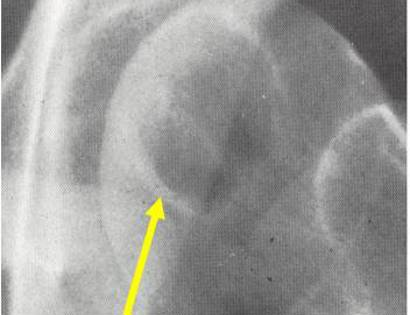

X-Ray of Clear Cell Chondrosarcoma

On an X-Ray, also called a radiograph, a clear cell chondrosarcoma can be diagnosed by looking at certain features. Most commonly seen in a clear cell chondrosarcoma is usually osteolytic, expansile lesion, that may be focally calcified, often a sharp interface between tumor and surrounding bone and the overlying cortex is usually thin, but intact.